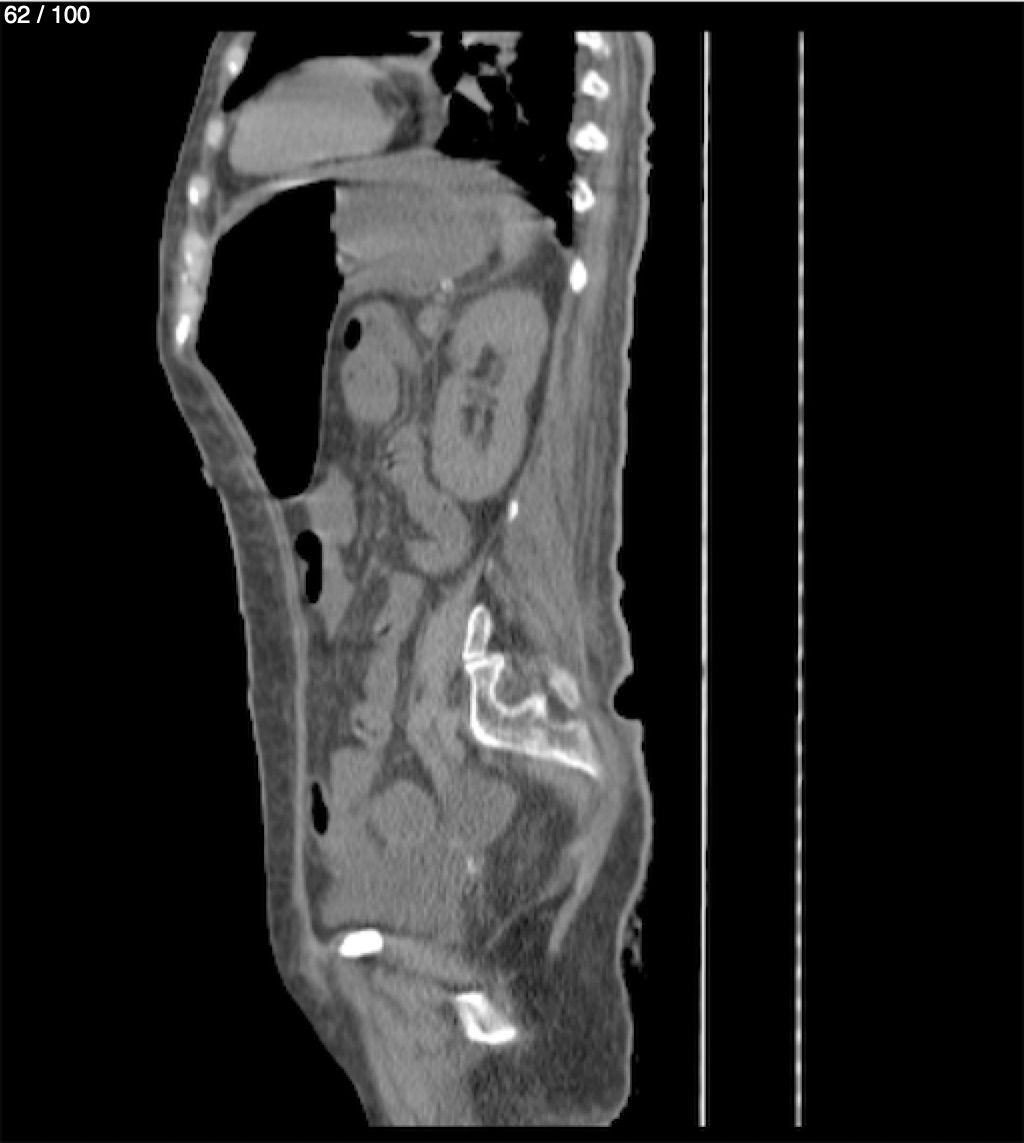

Hilda Geronimo Mendez 60A - T.C Abdomen Simple